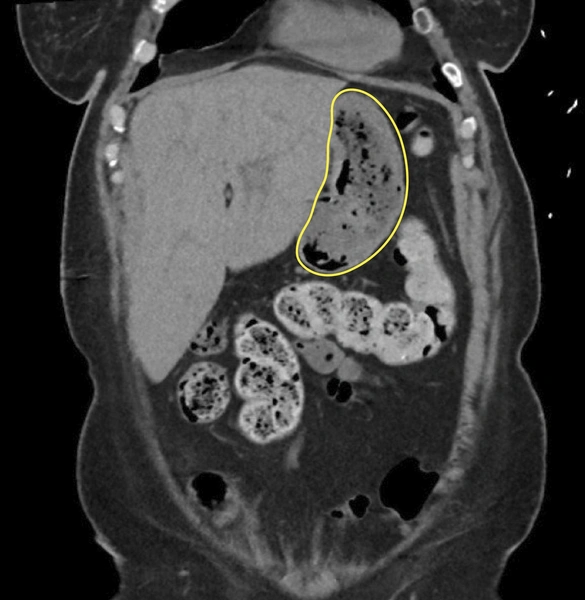

В ходе сканирования методом МРХПГ выявлено образование в желудке, напоминающее скопление воздуха. При эндоскопии обнаружен безоар — комок инородных тел, в данном случае остатков пищи, который не переварился и стал желудочным камнем.

Врачи столкнулись с необычным случаем — необходимо было избавить пациентку от безоара в желудке. Вместо стандартных методов удаления, они решили применить необычный способ лечения: растворить желудочный камень с помощью колы.

Исследования показывают, что кола может оказывать неожиданный эффект на организм. На второй день приема колы пациентка почувствовала тянущее ощущение в животе, но затем тошнота и дискомфорт быстро ушли. Это привело к тому, что повторная эндоскопия не выявила безоара.